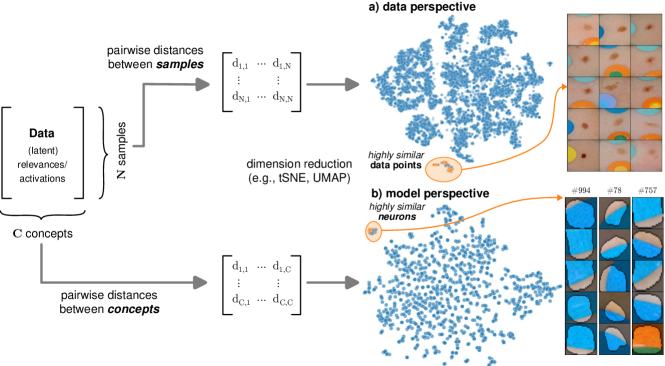

In contrast to detecting spurious samples, recent work focuses on identifying spurious model internals directly. This aligns with mechanistic interpretability, which seeks to decipher the internal mechanics of DNNs [56, 31, 13]. As outlined in Sec. 3.1, various global XAIs methods aim to explain the role of individual neurons, and these insights can be leveraged to detect spurious model internals by clustering learned concepts and identifying outliers. Given input data with samples, Pahde et al. [59] compute spatially aggregated relevances . Subsequently, they compute the pairwise cosine distance per column (i.e., channel/concept) and embed the resulting distance matrix in a low-dimensional space using dimension reduction techniques like t-Distributed Stochastic Neighbor Embedding (t-SNE) [71] or Uniform Manifold Approximation and Projection (UMAP) [49]. This low-dimensional embedding can be visualized to identify outliers through human inspection or anomaly detection algorithms, such as the Local Outlier Factor [12]. In summary, outlier representations can be identified in an embedding representation , obtained as

where reduces the dimension to , and the pairwise distance function is applied along all channel dimensions in the latent representation , either given by activations or relevance scores for layer . Note that this approach assumes over-parameterization resulting in redundant neurons, allowing to distinguish between similar and dissimilar concept representations. An example is shown in Fig. 4 (bottom), where latent relevance scores from a ResNet50 model trained for melanoma detection are used to identify outlier concepts, specifically a cluster focusing on band-aids rather than clinically relevant features. Notably, Eq. 3 can easily be extended to find outlier directions instead of neurons. Specifically, this involves a linear transformation of latent representations using the directions of interest, e.g., obtained in unsupervised manner as described in Sec. 3.1.

Data Perspective

We first apply SpRAy in input and latent space, computing input feature importance scores using LRP summed over color channels. To obtain latent relevances, we use intermediate relevance scores in the LRP computation process after the (out of four) residual block, max-pooling over spatial dimensions to yield relevance scores for layer with channels. The clustering of pairwise cosine distances between heatmaps is shown in Fig. 6 (top left). Detected outlier clusters contain samples with spatially coherent biases, e.g., the black circle around the lesions originating from microscopes (). In contrast, clustering latent relevance scores reveals more complex, less spatially dependent clusters, as shown in Fig. 6 (top right), including the ruler artifact () and the microscope (). Compared to those in input space, the cluster for the microscope in latent space represents a more diverse high-level concept. In the input space visualization, we further highlight samples from the ruler cluster detected in latent space. Instead of forming a cluster, they spread across the entire embedding space, indicating that the bias is too complex to be detected in input space.

Model Perspective

Next, we apply bias identification approaches from the model perspective by identifying outlier neurons based on activation pattern via DORA and relevance pattern by clustering pair-wise cosine distances between concept relevance scores. We focus on latent activations and relevances after the third residual block. DORA uses a distance function based on how neurons activate upon each others n-AMS, achieving high similarity when neurons activate upon similar input signal. A 2D visualization of the resulting distance matrix is shown in Fig. 6 (bottom left). Identified outlier concepts include ruler () and (white) hair (). We further compute pairwise cosine distances between latent relevance scores , aggregated over spatial dimensions, and apply UMAP to embed the resulting distance matrix in . This results in high similarity between neurons (concepts) that the model uses similarly for predictions. The concept clustering is visualized in Fig. 6 (bottom right), highlighting two outlier clusters focused on rulers () and blueish tint ().